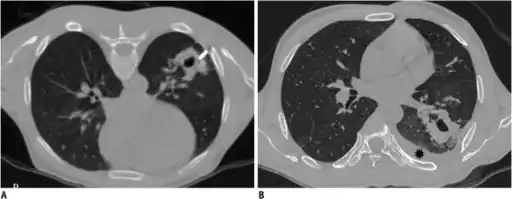

Chest X-ray

A chest X-ray is the most common technique used to diagnosis a hemothorax.[23] X-rays should ideally be taken in an upright position (an erect chest X-ray), but may be performed with the person lying on their back (supine) if an erect chest X-ray is not feasible. On an erect chest X-ray, a hemothorax is suggested by blunting of the costophrenic angle or partial or complete opacification of the affected half of the thorax. On a supine film the blood tends to layer in the pleural space, but can be appreciated as a haziness of one half of the thorax relative to the other.[5] A small hemothorax may be missed on a chest X-ray as several hundred milliliters of blood can be hidden by the diaphragm and abdominal viscera on an erect film. Supine X-rays are even less sensitive and as much as one liter of blood can be missed on a supine film.[24]